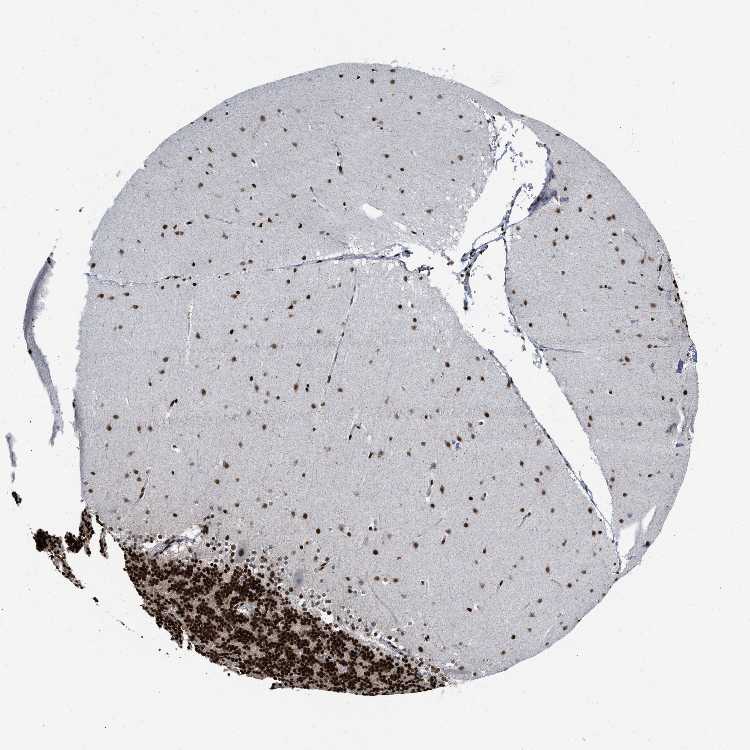

BRAIN CEREBELLUM Show tissue menu

CEREBELLUM - Antibody stainingi

Antibody staining in the annotated cell types in the current human tissue is reported as not detected, low, medium, or high, based on conventional immunohistochemistry profiling in selected tissues. This score is based on the combination of the staining intensity and fraction of stained cells.

Each image is clickable and will lead to virtual microscopy that enables deeper exploration of all samples and also displays staining intensity scores, fraction scores and subcellular localization as well as patient and tissue information for each sample.

Antibody HPA019150Antibody CAB003803

Cells in granular layer High-

Cells in molecular layer High-